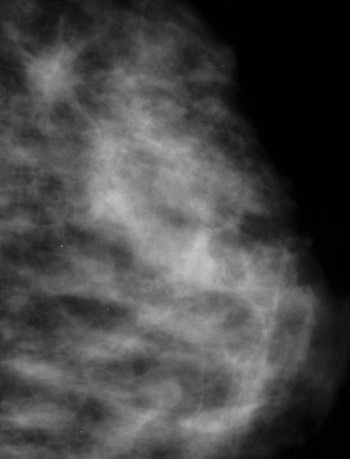

![]() |

| Very dense, glandular pattern seen on mammography in most young women. Breast cancer is extremely hard to find when the breast pattern is this dense, with almost no fatty tissue present. Image courtesy of Dr. Michael Linver. |

The challenge in such patients is to use the appropriate imaging modality, according to the experts. Dr. Thomas Kolb, a radiologist in private practice in New York City, was the lead author of a study published last year in Radiology that showed an inverse relationship between breast density and mammography sensitivity, and that dense breast tissue is more common in younger women (October 2002, Vol. 225:1, pp. 165-175).

He said that ultrasound can be a useful screening modality in at-risk young women. "In my practice, I do one or two screening ultrasounds per year in addition to an annual mammogram in high-risk young women," he said. He noted that screening MRI is also being investigated, although he cautioned that neither MRI nor ultrasound are widely accepted breast screening modalities.

"For women younger than 30, there is also some concern that the breast tissues may still be susceptible to radiation carcinogenesis, while the breast tissue of older women is probably fairly ‘radio-resistant,’" Kopans said. "Therefore, it is probably a good idea to limit breast radiation exposures to those cases where it is really medically indicated. Most health planners would argue that the benefit, when weighed against the risks and costs, does not support breast cancer screening before the age of 40."

Linver agreed with this assessment. "Thirty is the cutoff because the breast is more sensitive to radiation before that age," he said. "There is a minimal risk that can’t be ignored in those women, with some very special exceptions." Among women younger than 30 who want to be screened, a strong history must be present in order to justify mammography, he said.